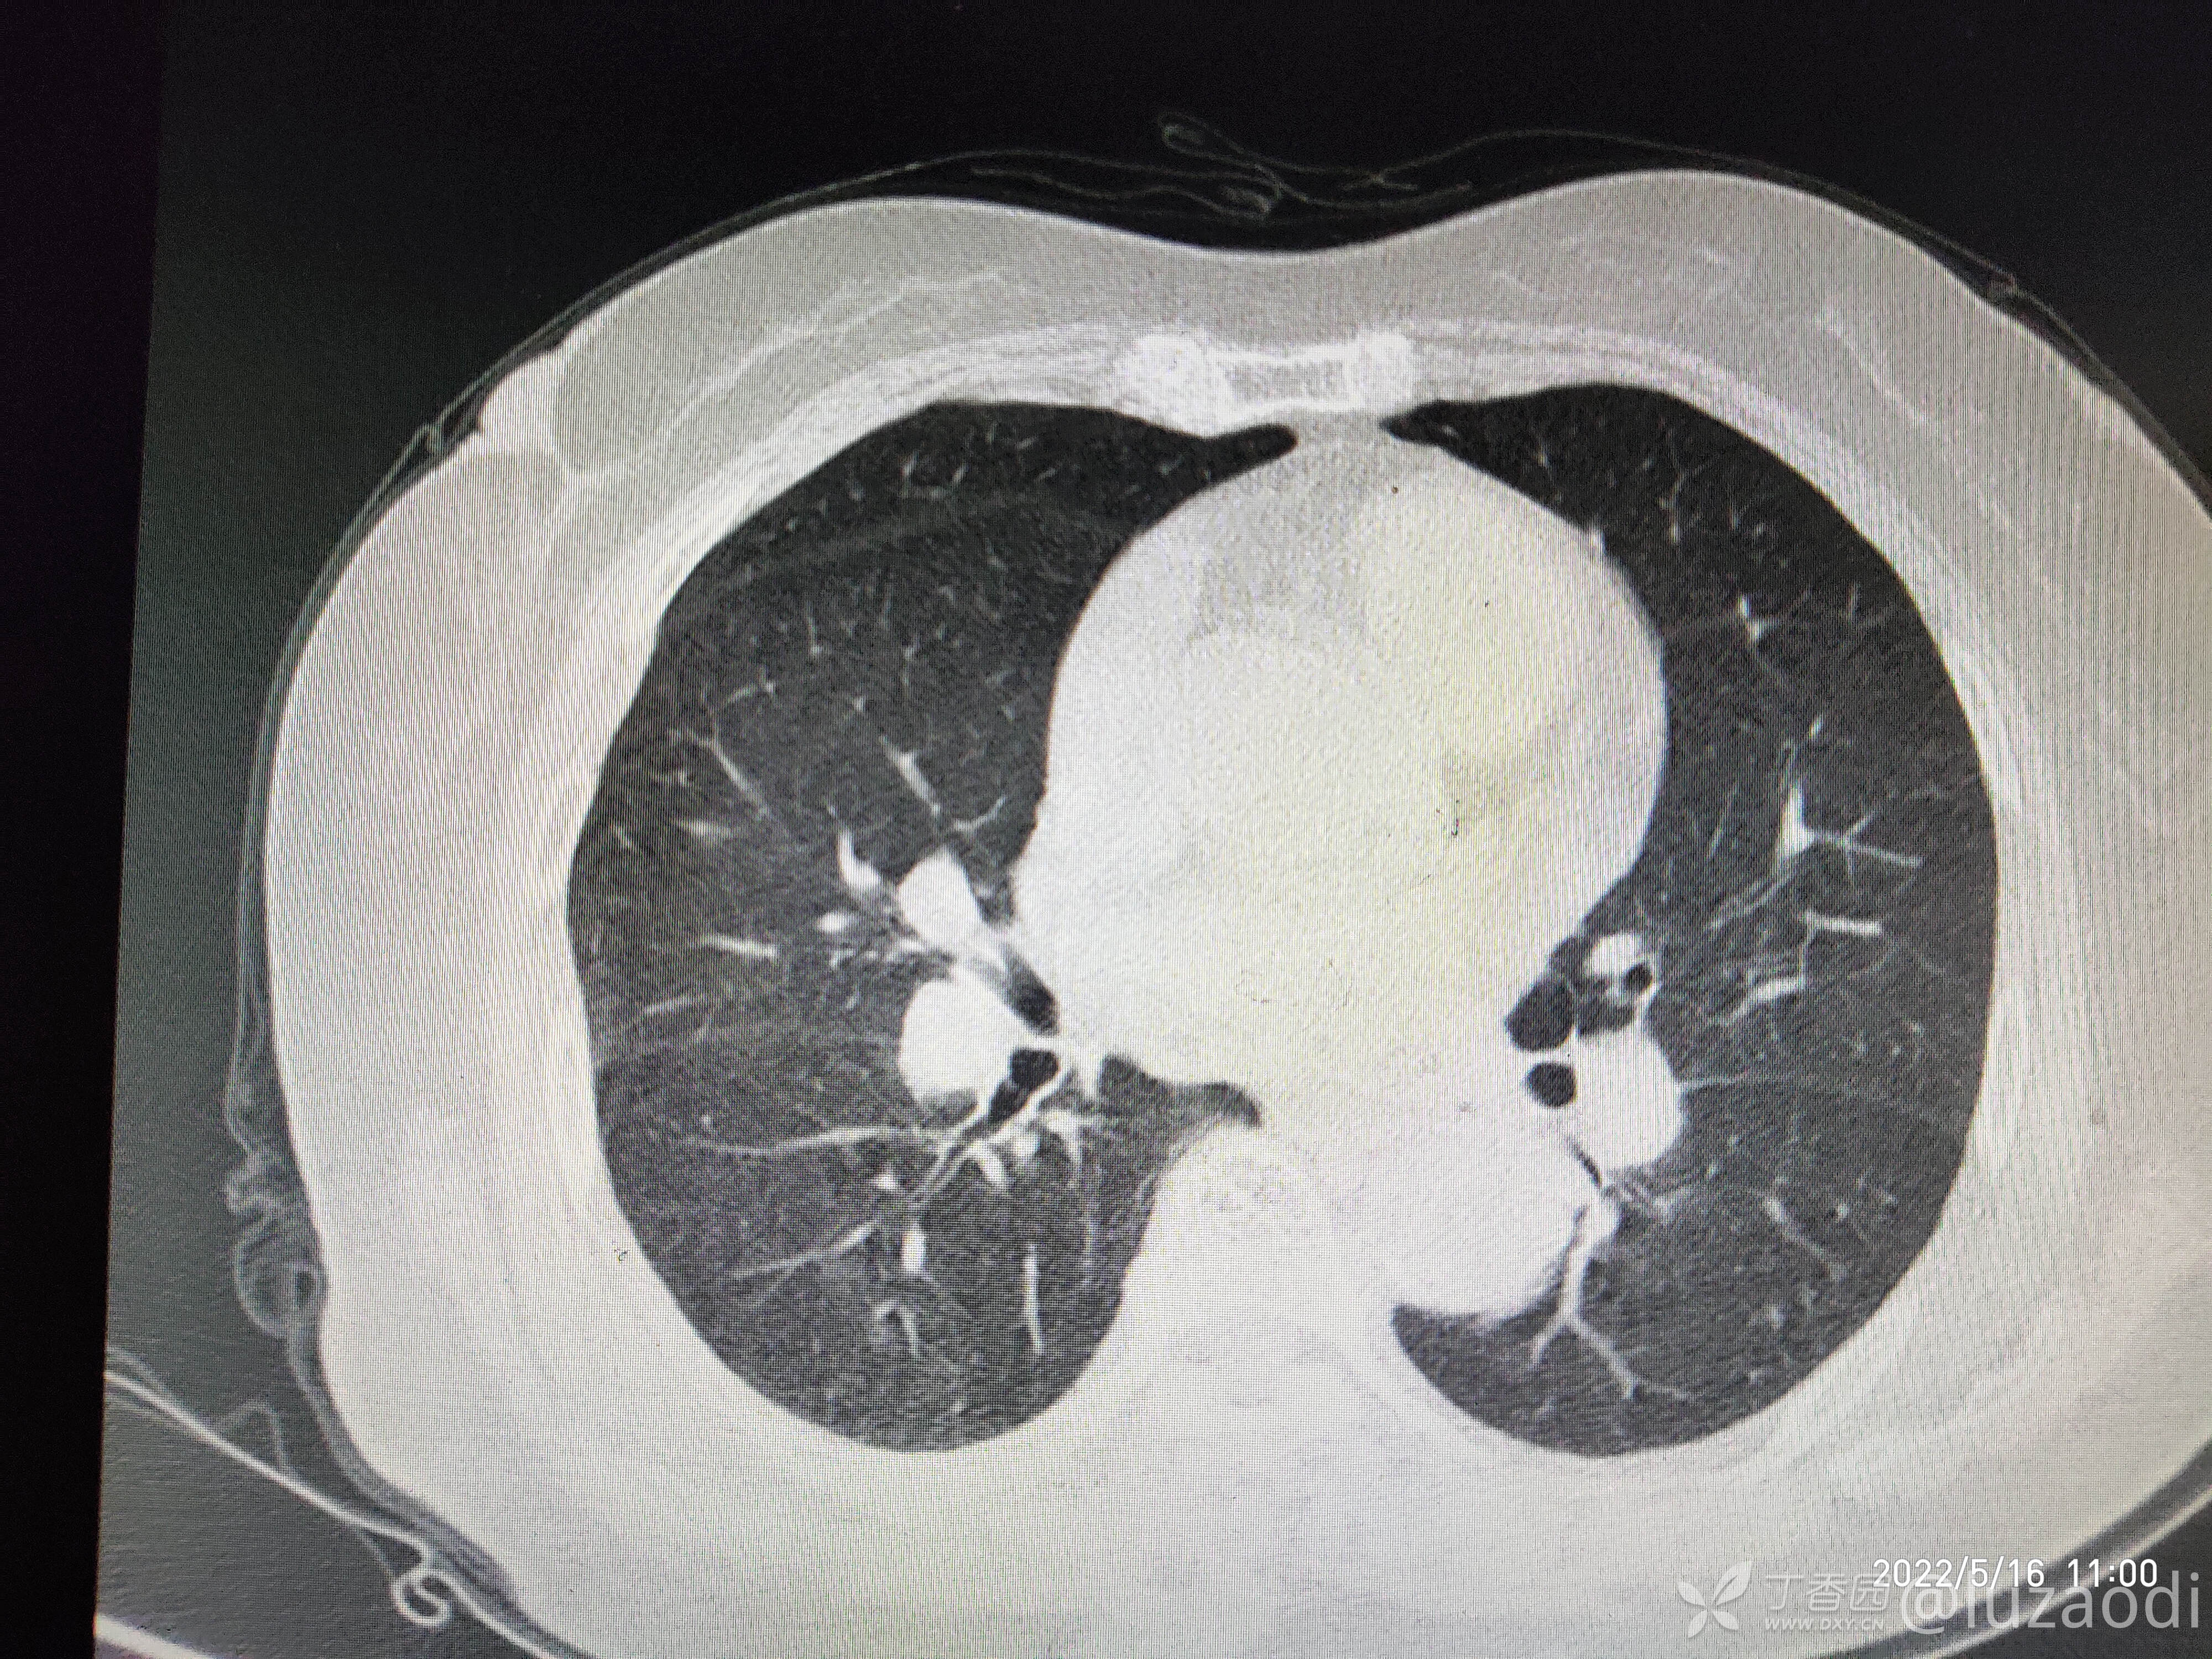

治疗经过:入院后患者仅有乏力,未见明显神经定位征。近期无发热、咳嗽、腹泻症状。遂予血糖、心电图、生化检查及影像检查,结果如下:

我去。。。。。视频只能上传一个,头颅CT上传不了,我直接说报告吧。头颅CT报腔隙性脑梗。